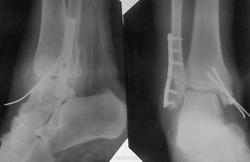

Пациентке 50 лет, в марте 2011 получила бытовую травму, при поступлению в одну из ЦРБ Нижегородской области был диагносцирован трехлодыжечный перелом, наружный подвывих стопы (рентгенограммы 1). Поскольку боковая рентгенограмма сделана с ротацией, никто не обратил внимания на передний отдел метаэпифиза б/берцовой кости. Пациентке налажено скелетное вытяжение (рентгенограммы 2,3), на боковом снимке видно повреждение переднего отдела метаэпифиза, но внимание на это не обращается, выполняется стандартный остеосинтез наружной и внутренней лодыжек (рентгенгограммы 4), опять же ни о кого не возникает никаких вопросов, а именно: почему дисконгруэнтна суставная щель, стопа в переднем подвывихе и в эквинусе. В августе пациентка приходит на контроль, и уже отчетливо виден дефект переднего отдела метаэпифиза б/берцовой кости, смещение костного фрагмента метаэпифиза кпереди и передний вывих стопы, но никаких мероприятий не проводится. Вчера, 9.02 пациентка все же доходит до нашего института, и мы видим такую картину (рентгенограммы 5,6): дефект переднего края дистального метаэпифиза б/берцовой кости, костный фрагмент смещен кпереди, некротизирован (фактически это секвестр), стопа в положении переднего вывиха, разрыв дистального межберцового синдесмоза, нестабильность металлоконструкций в б/берцовой кости (отчетливо видна резорбция), асептический некроз блока таранной кости. Прогноз неблагоприятен: артродезирование г/стопоного сустава, вопрос только в выборе метода, аппаратный артродез, либо ретроградный интрамедуллярный.